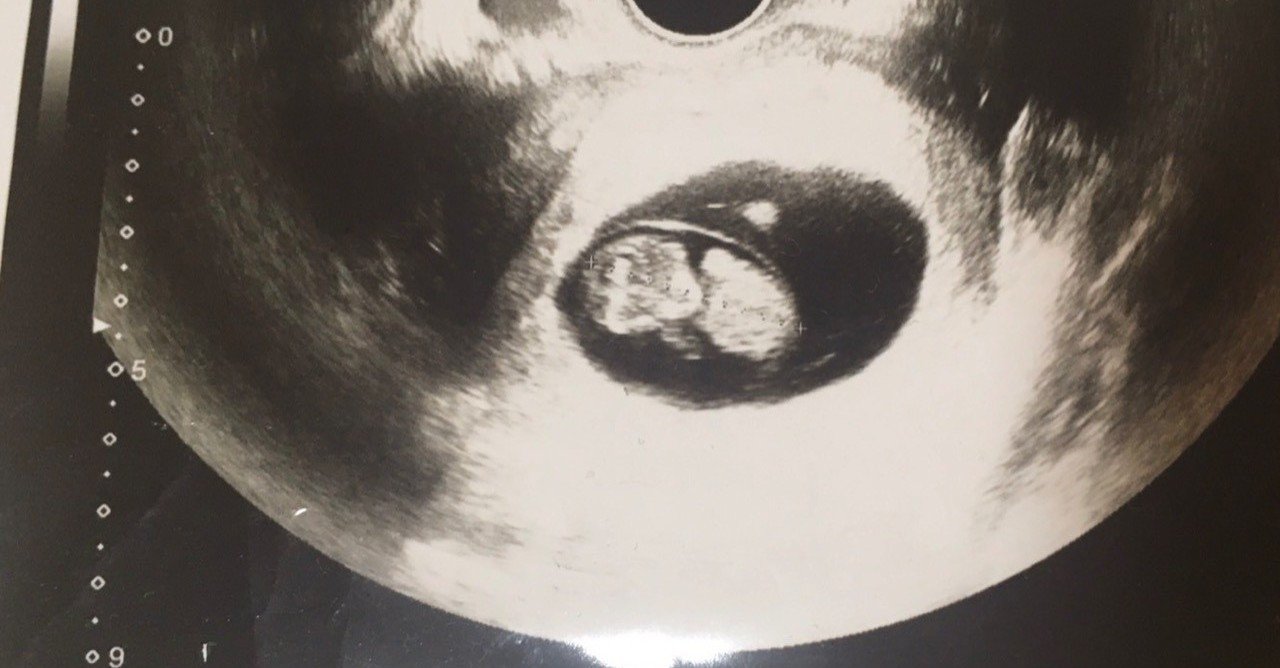

くろみつさんの妊娠6週目のエコー写真 心臓の動きが確認できてひと安心 エコー画像で振り返る、私に宿った小さな命が大きく育って誕生するまでの記録 おなかの赤ちゃんは元気でいるのかどうか不安だった2週間を経て、やっと検診の日が来ました妊娠4週になると見えてくる、「胎嚢」「卵黄嚢」って何? 妊娠5週になると脳や神経、心臓など臓器、それに手足や目、耳の原型もできるってホント? 妊娠6~7週で、心臓の動き出す!? まだ「胎児」と呼んでもらえない妊娠2ヶ月の「胎芽」時代の赤ちゃんのこと、母体のこと。 妊娠6週目は風邪のような症状 妊娠4週目、5週目と病院にいっていましたが、次回はgw明けに来てくださいといわれ、 急に診察が3週間ほど空くことになり不安度はmax。 具合悪いほうがよく育っているというわけでもないらしいんだけど、症状が軽いとそれはそれで不安

妊娠6週目 エコー写真 胎芽や胎嚢大きさ 心拍確認や気になる流産 妊娠初期 All About

医師監修 妊娠6週のエコー写真 心拍が確認できるころ マイナビ子育て

助産師監修 妊娠6週目 妊娠2ヶ月 エコー写真 心拍確認やつわり 出血について

6週目です 妊娠6週目1日のエコー写真です 胎嚢は確認できたのですが胎 Okwave